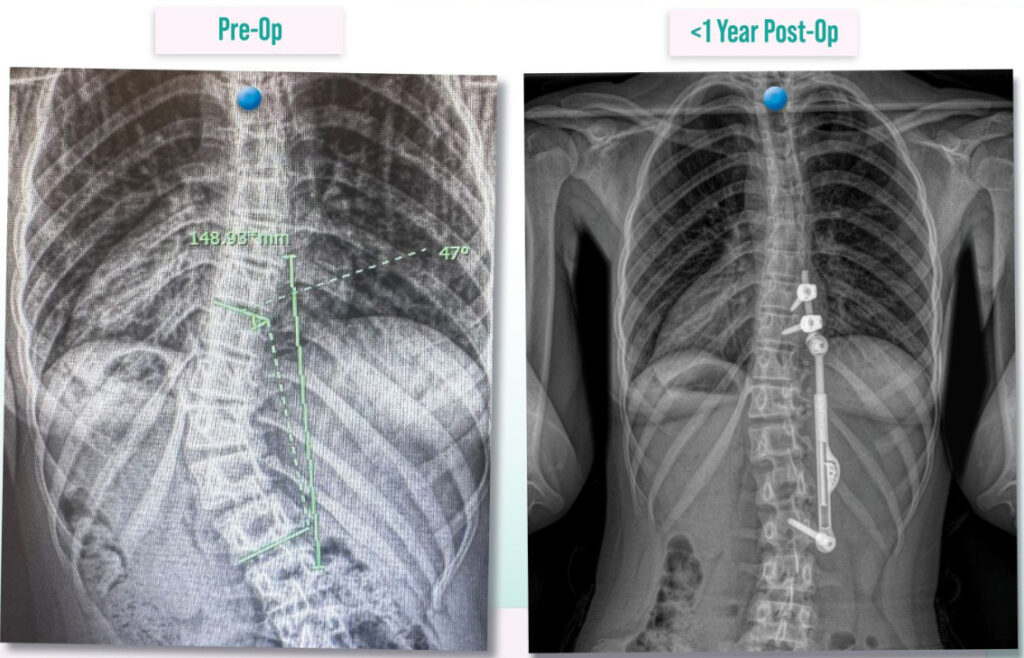

Apifix® Procedure (Non-Fusion Scoliosis Surgery)

Led by research-focused pediatric spine specialists, Apifix® Procedure is a unilateral technique designed for minimal invasiveness, preservation of growth and spinal flexibility, and reduced recovery times. It is designed especially for early-onset scoliosis.